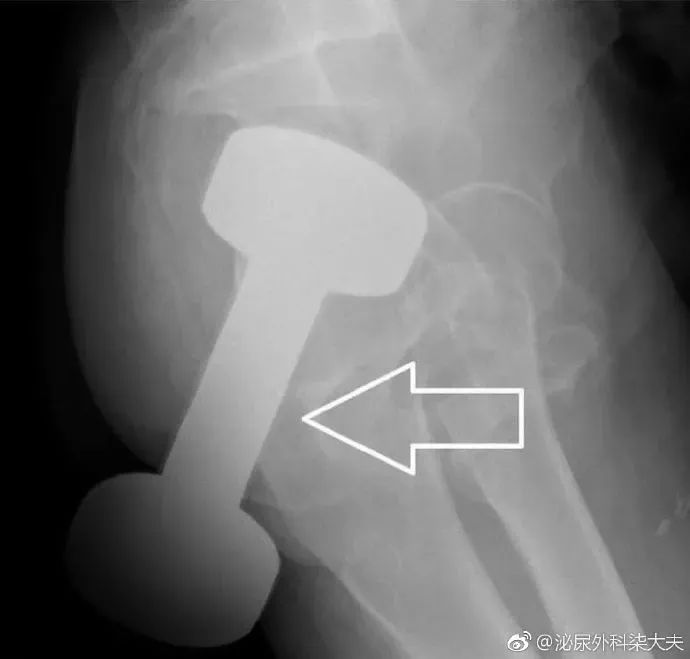

一位50多岁的男子发现了这种新奇玩法,把重达10斤的哑铃塞进了肛门。

罗非鱼直肠,罗非鱼塞进直肠多长时间